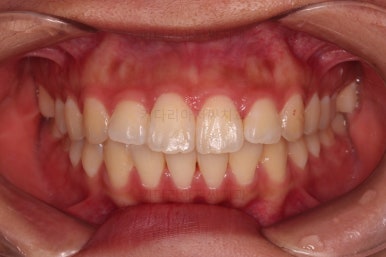

5. 마무리와 치료 종료

마무리가 잘 되었습니다.

큰 문제는 없었지만, 약간 삐뚤었던 치열이 가지런하게 정렬이 잘 되었고요.

맞물림도 매우 좋고, 뻗친 앞니 각도도 매우 좋아졌습니다.

입 안의 모습만 보면 최상급의 마무리가 되었고요.

이제 얼굴모습 변화 비교해 보겠습니다.